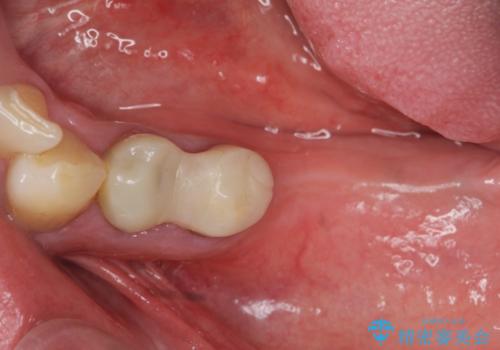

部分的な治療ではなく、全体的な治療を任せていただけたことで、清掃性の高く咬合関係の良い治療を行うことができました。

見た目の改善だけでなく、噛み合わせの仕上がりにも大変満足いただくことができました。